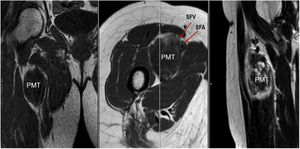

Sixty-one-year-old male, with no history of interest, assessed due to severe hypophosphataemia and treatment-resistant hyperphosphaturia. Clinically he suffered from general incapacitating bone pain and required crutches for walking. The images showed multiple bone lesions and fractures at several levels, with a prominent non-displaced sub capital fracture of the right femur. The PET/CT detected bilateral thyroid nodules with negative PAAF. The Tc-sestamibi marked bone scan presented focal uptake compatible with parathyroid adenoma, guiding diagnosis towards primary hyperparathyroidism (PHPT). A left hemithyroidectomy was performed resulting in normal parathyroid gland. Further analytic tests revealed hypophosphoraemia of 1.2 mg/dl, AF of 402 U/l and FGF23 of 247 U/l (n < 145). This finding guided diagnosis towards PMT, not initially detectable with NMR and PET/CT. A replacement medical treatment was selected, with the patient improving partially clinically and analytically. Due to the levels of FGF23 up to 357,2 U/l an octreoscan with no diagnosis was performed. Finally, repetition of the PET/CT detected an increase in metabolic activity in the right side of the body of L1 (Fig. 1). Following CT-guided needle core biopsy (NCB) a lesion compatible with PMT was diagnosed. Treatment consisted in percutaneous cryotherapy of the lesions guided by CT and simultaneous neurophysiologic control (Fig. 2). Phosphorous levels in blood and urine and FGF23 levels have normalised over time.

Sixty-two-year-old woman, with a history of left hemithyroidectomy due to nodular hyperplasia. Clinical symptoms began with general bone pain of 2 years onset, treated with NSAIDs. Following this, hypophosphataemia and hyperphosphaturia were found, AP of 273 U/l, severe radiographic osteopenia with vertebral T11-T12-L1-L2 fractures, with no trauma. Initially she was diagnosed with adult hypophosphoremic osteomalacia, and began medical treatment with phosphorous and calcitriol, which led to clinical improvement. After this, progressive impairment of renal function began with ongoing hypophosphataemia despite medical treatment. This led to chronic stage IV kidney disease with bilateral cortical nephrocalcinosis. Consecutively, elevation of PTH to 1.212 pg/mL, FGF23 to 415 U/l (n < 145), creatinine to 2.72 mg/dl and phosphorous to 1.7 mg/dl were detected. With these results, the octreoscan detected uptake in the right groin, with soft tissue mass at that level. After the NMR (Fig. 3) an ultrasound-guided CNB resulted in PMT. Extended resection was performed (Fig. 4) with histological confirmation of PMT, mad immediate analytical normalisation. Unfortunately this patient presented with chronic complications of hypophosphataemic rickets, SHPT and nephrocalcinosis.

Forty-six-year old male, with no history of interest, with an onset of radiating low back pain in 2012 after effort. The initial NMR presented L5-S1 central vertebral disk hernia ion and L3-L4 left lateral and foramina vertebral disk herniation with no improvements of symptoms following conservative treatment. Decompression and instrumented arthodesis at L3-S1 levels was carried out in September 2013. His condition clinically worsened and he had difficulty walking, needing 2 crutches and finally a wheelchair. During follow-up we observed pseudo osteoarthritis at the levels where he had been operated on and an aseptic loosening of instrumentation. Further intervention took place in 2014, with removal of previous material, insertion of new material and the addition of a graft. Evolution was poor with a third operation required in June 2015. Intersomatic lumbar cages with a new autologous graft were added through anterior approach. Lack of improvement led to a bone metabolism study which showed hyperphosphaturic hypophosphataemia and raised FGF23 levels. A left femur neck fracture also occurred. The octreoscan revealed an increase in activity in the right heel footpad. The NMR confirmed soft tissue lesions (Fig. 5). Finally, given the small size of the lesion and high diagnostic suspicion, extended resection was performed, confirming PMT. The patient evolved favourably, with clinical and analyticla normalisation, and was able to perform daily life activities independently. Unfortunately he has required total bilateral hip replacements due to osteonecrosis at this level.